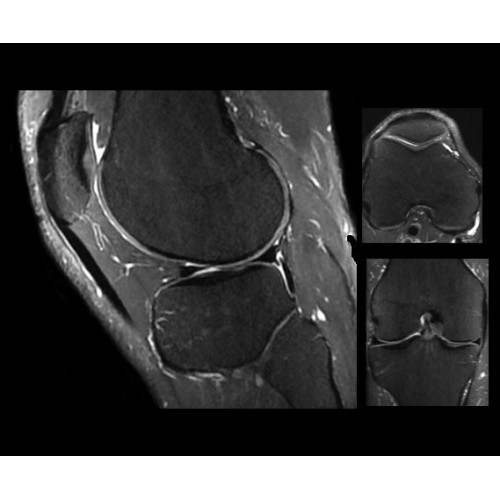

SIGNA PET/MR 3.0T — это гибридная система, в которой совмещаются две принципиально разные технологии — магнитно-резонансную томографию (МРТ) и позитронно-эмиссионную томографию (ПЭТ). Система отличающийся высокой чувствительностью и эффективностью и предназначена для диагностики в области онкологии, неврологии, кардио-васкулярных исследований, исследований воспалительных процессов.

Компания GE Healthcare представляет революционную, полностью интегрированную систему SIGNA PET/MR1, в которой сочетаются времяпролетная технология (TOF) и возможности напряженности магнитного поля 3.0 Тл. Мы поможем вам поднять исследования на более высокий уровень. SIGNA PET/MR позволяет достичь впечатляющей точности и скорости исследований, а благодаря новейшей технологии реконструкции Q.Clear2 качество изображений улучшается в два раза. Кроме того, в систему включен полный набор клинических приложений и гибких катушек для проведения любых видов исследования, открывая для вас возможности визуализации, о которых вы даже не догадывались.

Система SIGNA PET/MR предлагает впечатляющие клинические возможности и открывает доступ к наиболее полным пакетам программных приложений.

Стандартный пакет приложений SIGNA Works позволит вам достичь желаемых результатов в клинической практике благодаря набору высокоэффективных средств визуализации. Программные приложения, входящие в состав данных клинических пакетов, включают широкий спектр контрастов, функции обработки 2D- и 3D-данных, а также возможность коррекции артефактов движения. SIGNA Works предоставляет набор инструментов, необходимых для проведения эффективного клинического исследования.